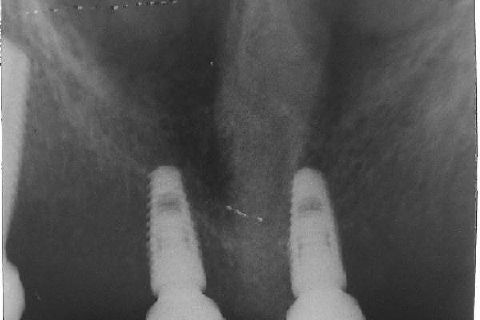

Atualização do caso clínico que já postei, "REABILITAÇÃO EM MAXILA ATRÓFICA COM IMPLANTES", um caso que inclui expansão do rebordo estreito com cinzel e martelo, expansores rosqueáveis, enxerto e instalação dos implantes distais inclinados tangenciando seio maxilar. Inclui esvaziamento do forame nasopalatino e preenchimento com biomaterial para instalação de dois implantes próximos dele. Cirurgia realizada em única sessão, com instalação dos 6 implantes. Para os colegas que não conheceram e/ou esqueceram da apresentação, este é o resumo do caso na fase cirúrgica.http://www.youtube.com/watch?v=BtvexFexRPA&hd=1

FASE PROTÉTICA DA REABILITAÇÃO EM MAXILA ATRÓFICA...incluindo a reabertura, instalação dos minipilares e PTR provisória reembasada sobre os cilindros de proteção.